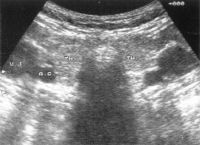

uh-kep-pajzsmirigy-jo-d00000E7D95e60039f2a3

Forrás: EgészségKalauz

Pajzsmirigy-ultrahang vizsgálat. Szemben az izotóp-vizsgálattal és a tapintással a pajzsmirigy mélyen elhelyezkedő, a bőr felszínétől távoli és ezért nem tapintható részeit is vizsgálhatóvá tette. Két nagyon fontos sajátsága alapján is a legjobb képalkotó módszernek tekinthető.

A pajzsmirigy-ultrahang-vizsgálatnak semmilyen szövődménye nincs, várandós kismamánál is nyugodtan el lehet végezni.